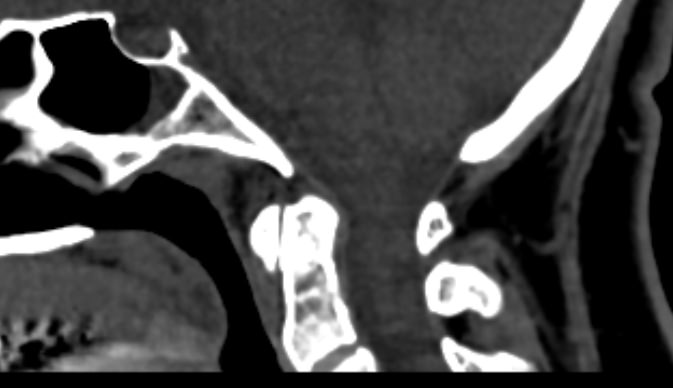

К краниовертебральной области относится первый шейный позвонок (атлант), второй шейный позвонок (аксис) и затылочная кость черепа. Атлантозатылочный сустав обеспечивает кивательные движения головы. Соединение первого и второго шейных позвонков состоит из трех мелких суставов и позволяет совершать вращательные движения головой.

Одним из наиболее информативных методов диагностики заболеваний краниовертебрального перехода является мультиспиральная компьютерная томография с возможностью объемной реконструкции изображений. В основе методики лежит использование рентгеновского излучения. КТ позволяет детально визуализировать костные структуры позвонков, выявить нестабильность суставов, смещение зубовидного отростка и оценить степень сдавления спинного мозга.

При проведении мультиспиральной КТ можно диагностировать различные заболевания, в том числе, аномалии развития краниовертебральной области (как врожденного, так и приобретенного происхождения):

- базилярная импрессия (выпячивание зубовидного отростка аксиса в большое затылочное отверстие); ассимиляция атланта (сращение первого шейного позвонка с затылочной костью); атланто-аксиальная дислокация (смещение первого и второго шейных позвонков по отношению друг к другу);